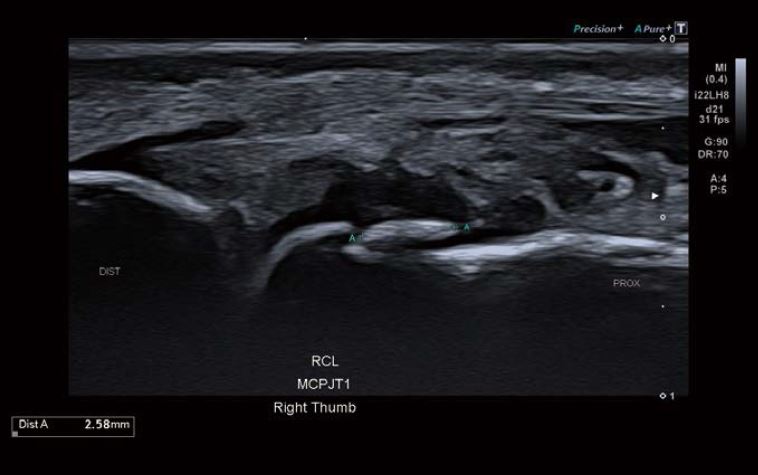

Зображення 3 На зображенні ПКЗ великого пальця видно 2,5 мм ехогенну ділянку у проксимальному відділі зв'язки, що вказує на уламковий перелом.